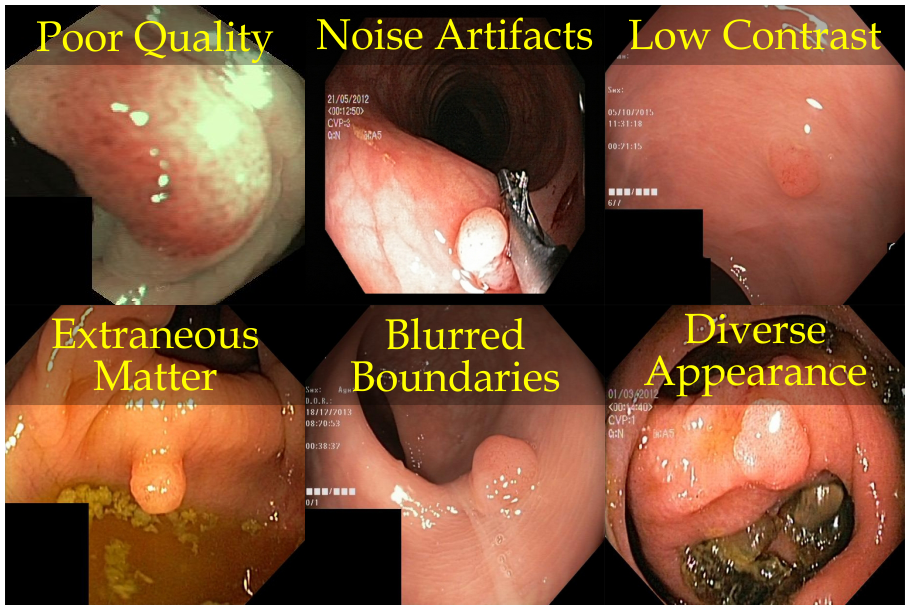

Automated gastrointestinal polyp segmentation presents significant challenges due to various factors illustrated in Fig. 1(b). Uneven illumination from body fluid reflection can degrade image quality, while noise artifacts like surgical instruments and intestinal contents complicate segmentation. Low contrast between tissues hinders accurate polyp localization and identification. Additionally, residual stool and digestive fluids can obscure internal tissues, making differentiation difficult. Polyp boundaries are blurred or unclear due to similar appearance patterns. Furthermore, inter-patient variability and diverse polyp types exhibit various colors and textures. Moreover, an imbalance in pixel distribution, as shown in Fig. 1(c), with the background area often exceeding the polyp area, introduces noise that affects segmentation performance.